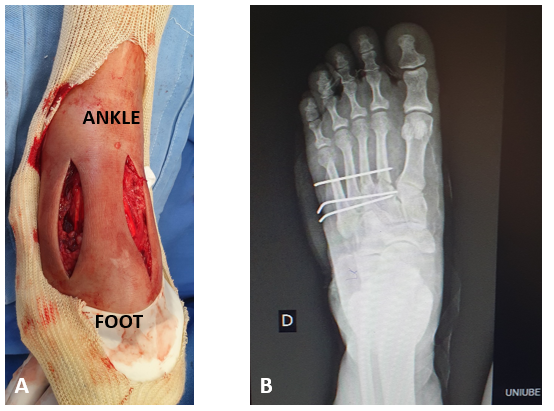

Female patient, forty-four years old, domestic, no comorbidities, sought care in an Emergency Care Unit, due to blunt trauma on right foot (five kilograms object drop), after approximately 2 hours. On orthopedic physical examination, she presented edema (3+/4+) and significant pain on dorsum of right foot, without neurovascular injuries. The radiograph and computed tomography of the foot showed fractures at the base of the 2º, 3º and 4º metatarsal, with no joint damage (Figures 1A & 1B).

Figure 1 Radiograph (A) and computed tomography imaging (B) of the foot indicating fracture at the base of the 2º, 3º and 4º metatarsal. Source: Author’s personal arquive.